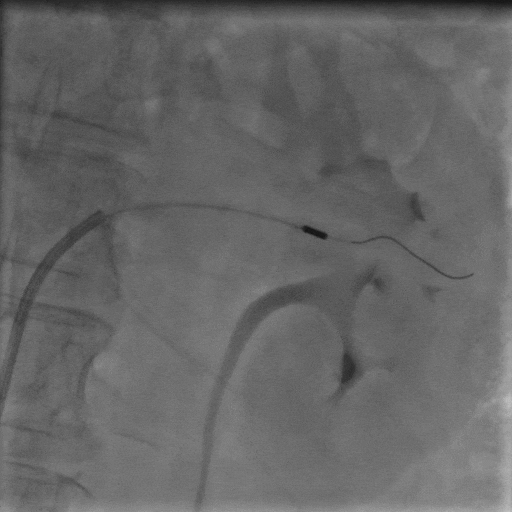

手術(shù)中,團(tuán)隊(duì)通過(guò)穿刺右側(cè)股動(dòng)脈,置入動(dòng)脈鞘和導(dǎo)管,對(duì)左右腎動(dòng)脈進(jìn)行造影評(píng)估后,使用Hawk Sonic超聲消融導(dǎo)管對(duì)腎動(dòng)脈分支及主干進(jìn)行消融治療。

術(shù)后患者血壓顯著下降,復(fù)測(cè)血壓149/72mmHg;手術(shù)次日血壓降至122/66mmHg,且術(shù)后2個(gè)月未發(fā)生任何不良事件,復(fù)查腎動(dòng)脈CTA未見(jiàn)狹窄等異常。

▲左側(cè)腎動(dòng)脈分支超聲消融